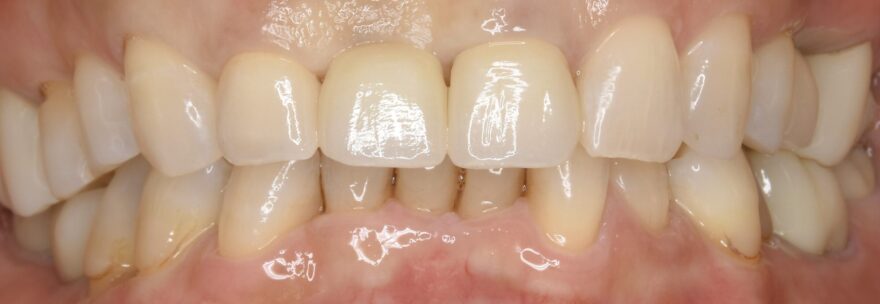

治療後の口腔内写真

なおインプラントの両サイドにはセラミック歯を被せてます。

治療後のレントゲン写真

精密に施術されたインプラントは20年30年とトラブルなくお使い頂けます。